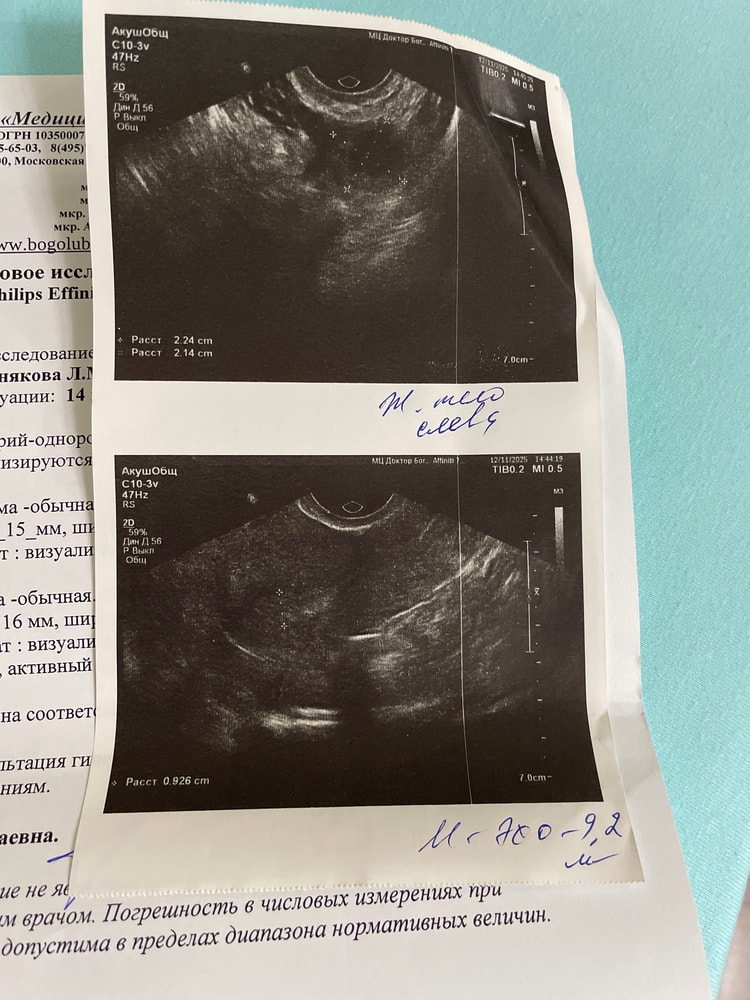

Всем приветик. 7 ноября был 9 дц, по узи людоминантный фоликул 19 мм, эндометрий 7 мм, 8 ноября мы с мужем волшебничали в ночь на 9 ноября. 10 ноября у нас была долгая поездка, сутки в дороге, сутки там и сутки обратно. Утром 10 ноября тест на овуляцию прям горел. Вчера 12 ноября сделала узи, желтое тело 22 мм, эндометрий 9 мм. Вот теперь думаю какой у меня сегодня дпо? И получилось ли у нас с мужем попасть до овуляции? Не рано ли?

У вас овуляция скорее всего была или между 11 ноября (вечер или ночь) или 12 ноября (раннее утро, время до узи). ПА был за 2,5 - 3 суток до овуляции. Если у вас по здоровью все хорошо, то зачатие возможно, т.к. сперматозоиды живут 3-5 суток. Сегодня у вас 1-2 дпо

У меня когда тест на О прям горит, то О в те же сутки. Но учитывайте, что у всех разный организм. Я думаю у вас О состоялась в течении суток после положительного теста.